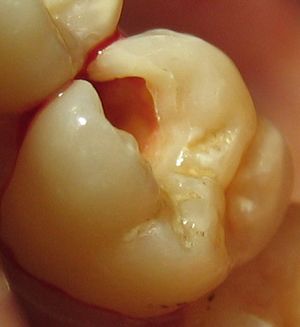

치아 수복 준비 과정의 예시. 윗쪽 어금니상아질이 썩어 제거되어, 바깥쪽 치아 에나멜이 지지받지 못하는 모습이다.

4. 1. 치아 준비

치아를 좋은 형태와 기능으로 복원하려면 먼저 수복 재료를 넣을 공간을 만들고, 구조적으로 약해진 썩은 부위나 일부분을 제거해야 한다. 이 과정을 치아 준비라고 한다. 보통 치과용 핸드피스와 버를 사용하거나, 치과용 레이저 또는 공기 연마로 치아를 다듬는다. 무외상 수복 치료의 경우 수기구를 사용하기도 한다.[5] 치아 준비 후 바로 영구 수복을 할 수 없을 때는 임시 수복을 하여 치아를 보호한다.

준비된 치아는 금, 아말감, 치과용 복합 레진, 글래스 아이오노머 시멘트, 도자기 등의 수복 재료로 채운다.